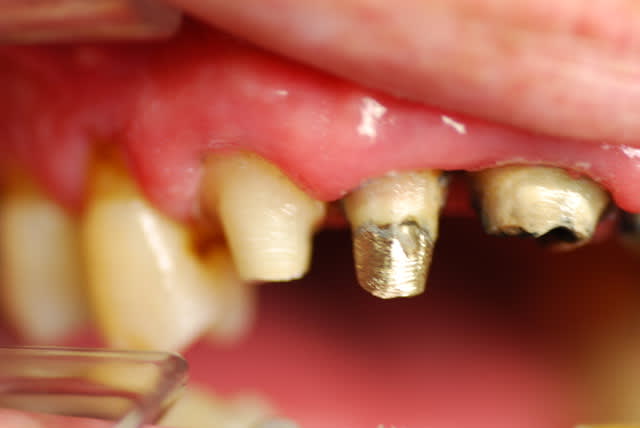

Je viens de revoir le patient et je peux vous apporter quelques précisions ainsi que des photos( désolé si la qualité n'est pas parfaite).

Patient de 45 ans, fumeur, motivé mais ne pouvant se payer d'implants.

Il a déjà vu plusieurs confrères qui lui ont proposé uniquement ( selon ses dires) une solution implantaire pour 12-11-21-22-23. Il souhaite du fixe...

En ce qui concerne la paro, la 12 est en mobilité stade 2, la 22 en stade 1 les autres étant non mobiles. Le sondage de 12 à 22 est de 3 mm, sauf en mésiale de 12 ( 6mm). La gencive est inflammatoire ( logique à la vue de l'inadaptation des couronnes, et des caries radiculaires).

Je pense lui proposer la solution du bridge avec 13,11,21,22, 24,25., même si la 13 est saine... Je prévoyais de reprendre l'endo de 22 mais la taille du tenon et sa longueur m'ont refroidi, peut être qu'une chir endo et obturation à rétro serait plus appropriées... Je prévois bien sur un surfaçage ainsi qu'un assainissement paro, une fois le bridge provisoire en place.